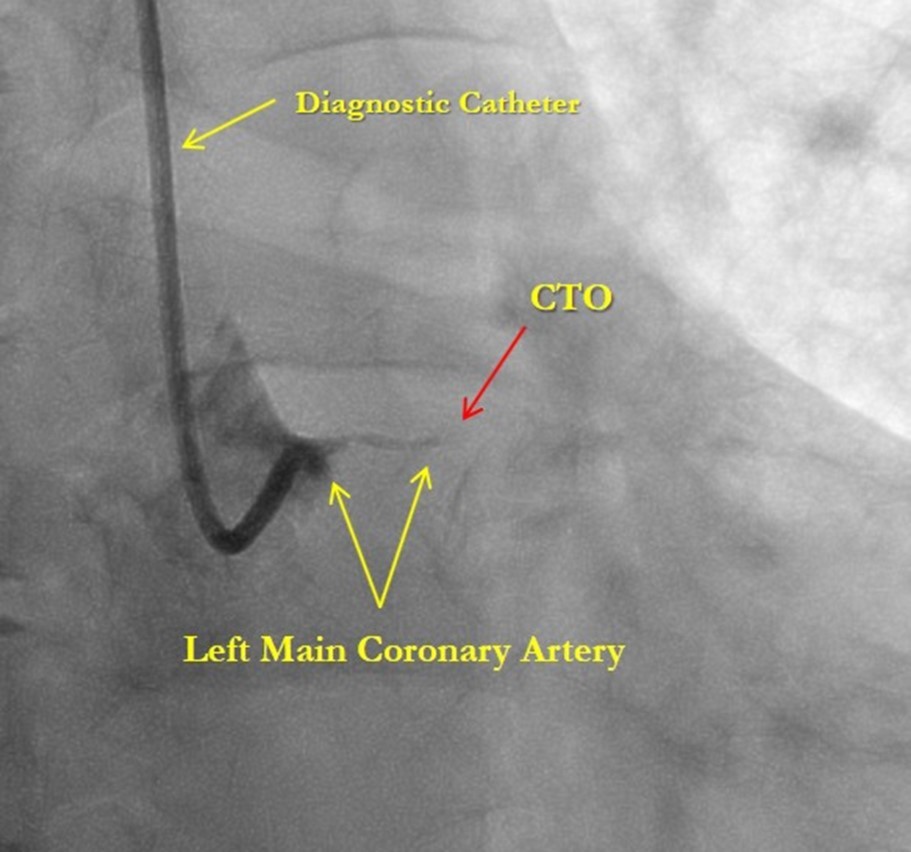

After medical treatment and comparable improvement in the patient's condition, expected risks were re-evaluated. After consulting with the patient and family members (they did not agree to the operation based on past experience) it was resolved to perform repeated CAG and to attempt revascularization of the LAD artery, (stenting). However, repeated CAG additionally revealed chronic 100% occlusion of the LMCA (Figure 1), and also CX occlusion, which was unexpected, and thereby significantly decreasing the likelihood of procedural success. In this case, the patient's heart was supplied only through the right coronary artery, which partially supplies the occluded left anterior descending and circumflex arteries through the contralateral collateral blood flow (Figure 2). Acute LMCA occlusion in most of the cases is fatal and survival is possible only in patients with a dominant RCA providing sufficient collateral formation.

Figure 1.Chronic total occlusion of the left main coronary artery